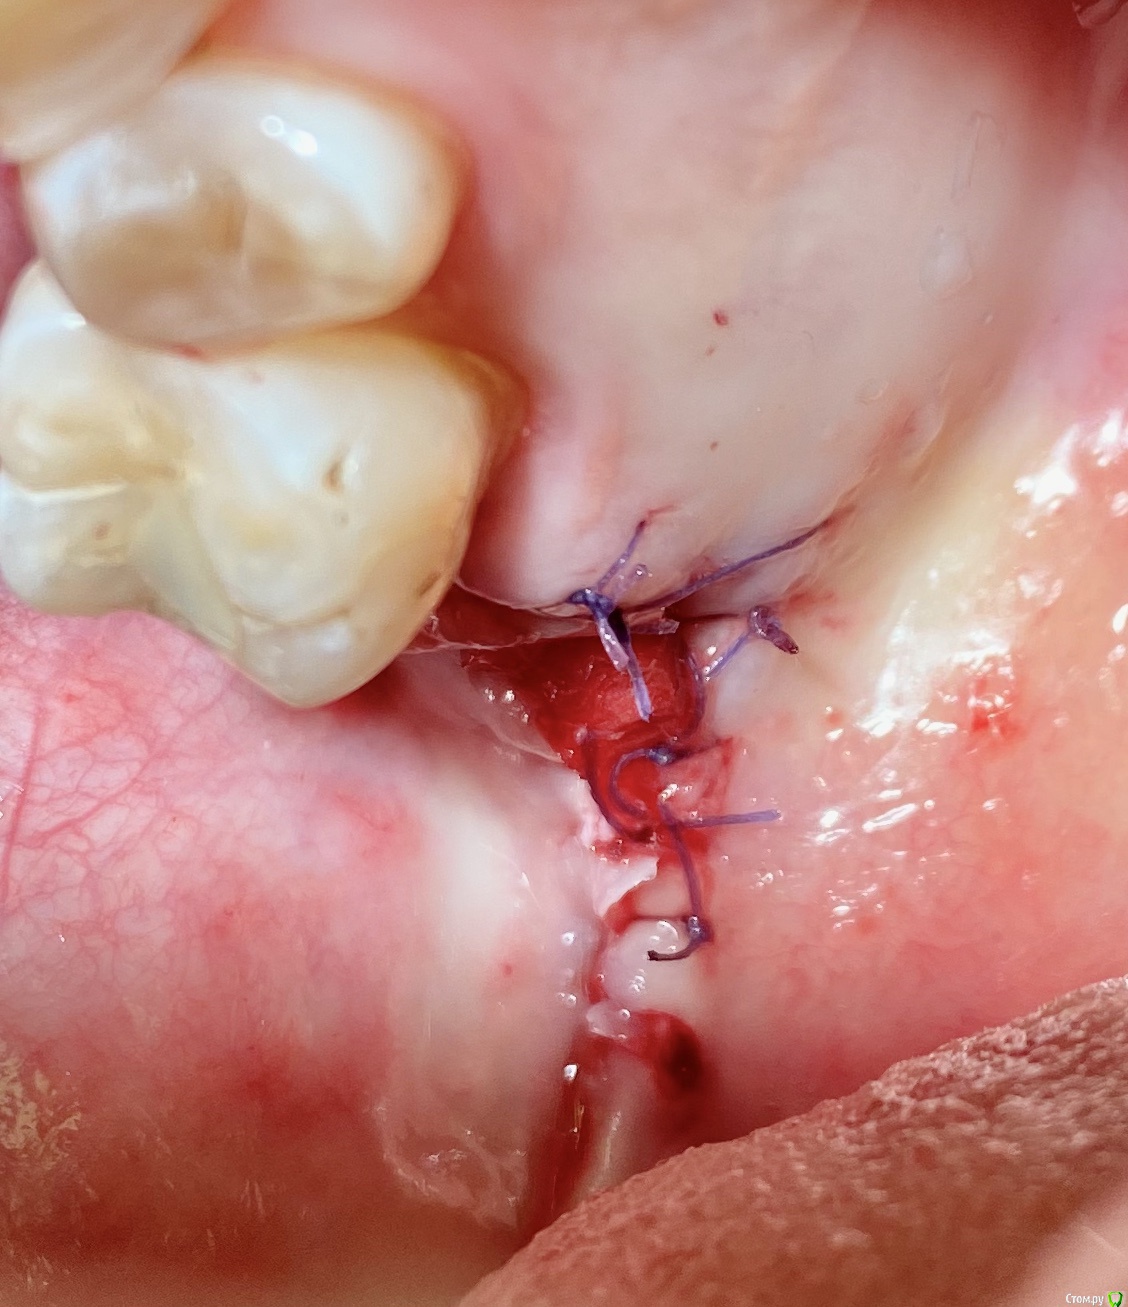

колесников Опубликовано 11 сентября, 2020 Поделиться Опубликовано 11 сентября, 2020 Перемещение бугра для закрытия лунки. Вестибулярно прикрепленную не смещаем. Вестибулярно компактной пластинки нет 9 Ссылка на комментарий

колесников Опубликовано 27 сентября, 2020 Поделиться Опубликовано 27 сентября, 2020 Вид через 2 недели Ссылка на комментарий